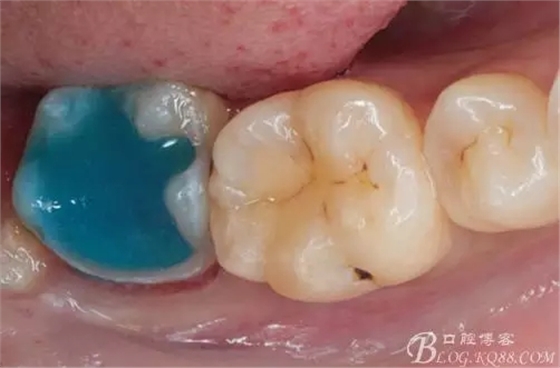

去除暫封物,拍照,比色。

流動(dòng)樹脂充填窩洞,金霸王車針和鎢鋼車針常規(guī)備牙,配合硅膠尖拋光,頰側(cè)排00排齦線。硅橡膠二次法取模,記錄咬頜關(guān)系,臨時(shí)樹脂充填窩洞。